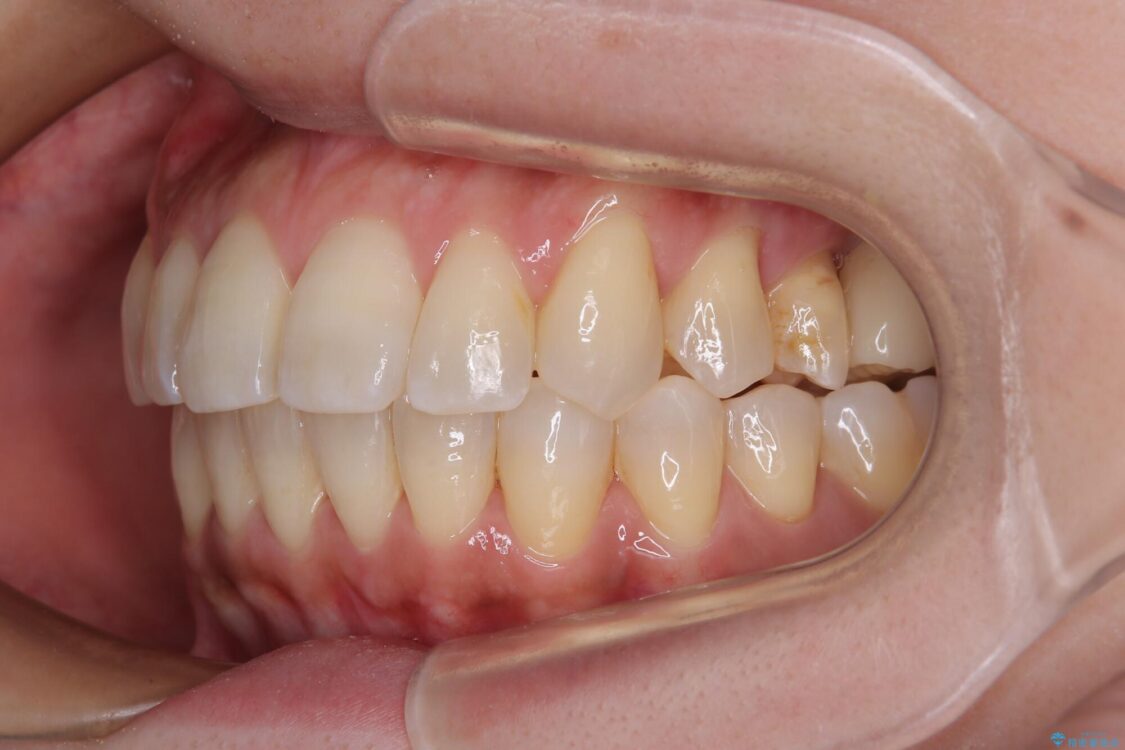

治療後

• インビザラインによる矯正治療と奥歯のインプラント治療 治療後画像

歯の傾斜が改善され、インプラントによるクラウンが装着されたことで、物が挟まることもなくなりました。

インビザライン矯正で全体の歯列と整えるとともに、左上第一大臼歯部にはスペースを作り、インプラントによる補綴治療を行うこととしました。